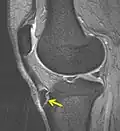

Rayos X mostrando la enfermedad de Osgood-Schlatter -

MBq Osgood-Schlatter, flecha mostrando la enfermedad -